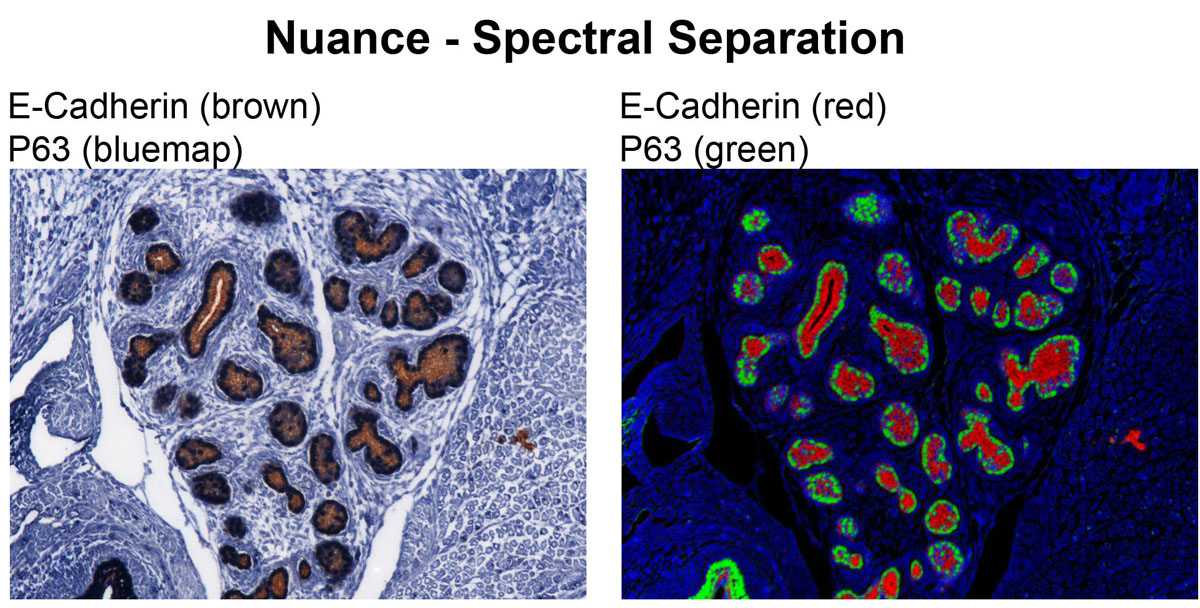

CRI Nuance (Zeiss Axioplan2 Upright Stand) - Nuance is a spectral scanning camera equipped on Zeiss Axioplan 2 upright widefield microscope. This camera has tunable filter that detects signals in spectral range of 420 nm to 720 nm. Multispectral microscopy allows separation of multiple signals with different spectral characteristics. Therefore, fluorophore with very close emission spectra can be distinguished from one another, and autofluorescence can be eliminated from specific signals. This system works not only with fluorescence but also with bright field images with chromatic (color) signals. It allows DAB signal to be separated from Hematoxylin counterstain.

CRI Nuance (Zeiss Axioplan2 Upright Stand) - Nuance is a spectral scanning camera equipped on Zeiss Axioplan 2 upright widefield microscope. This camera has tunable filter that detects signals in spectral range of 420 nm to 720 nm. Multispectral microscopy allows separation of multiple signals with different spectral characteristics. Therefore, fluorophore with very close emission spectra can be distinguished from one another, and autofluorescence can be eliminated from specific signals. This system works not only with fluorescence but also with bright field images with chromatic (color) signals. It allows DAB signal to be separated from Hematoxylin counterstain.